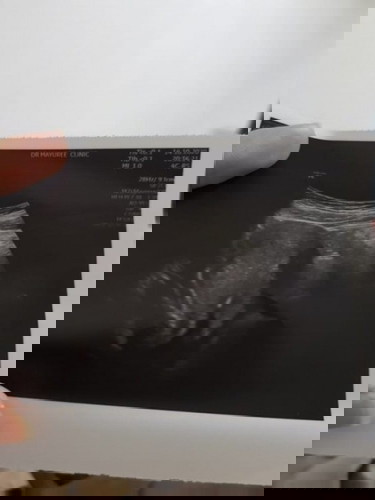

ต่อเนื่องจากเมื่อวานที่มีการตรวจฉี่ แล้วขึ้น 2 ขีด จางๆ ทั้งตอนเย็นวันที่ 13 และตอนเช้าวันที่ 14 เย็นวันที่ 14 ถึงไปหาหมอให้หมอตรวจอัลตร้าซาวด์ ปรากฏว่าหมอบอกว่ายังไม่เจอถุงน้ำคร่ำนัดให้ไปตรวจอีกรอบต้นเดือนพฤศจิกายน และให้ยาบำรุงมาทาน ซึ่งปกติรอบเดือนของเดือนที่แล้วที่มาวันแรกคือวันที่ 1 กันยายน ตอนนี้มีความกังวล มากๆค่ะ ถามหมอว่ามีโอกาสจะเป็นอย่างอื่นหรือไม่ หมอก็บอกว่าอาจจะเป็นเพราะ อายุครรภ์น้อยมากๆเลยยังมองไม่เห็น มีใครเป็นลักษณะแบบนี้ไหมคะ #ขอบคุณสำหรับคำตอบค่ะ